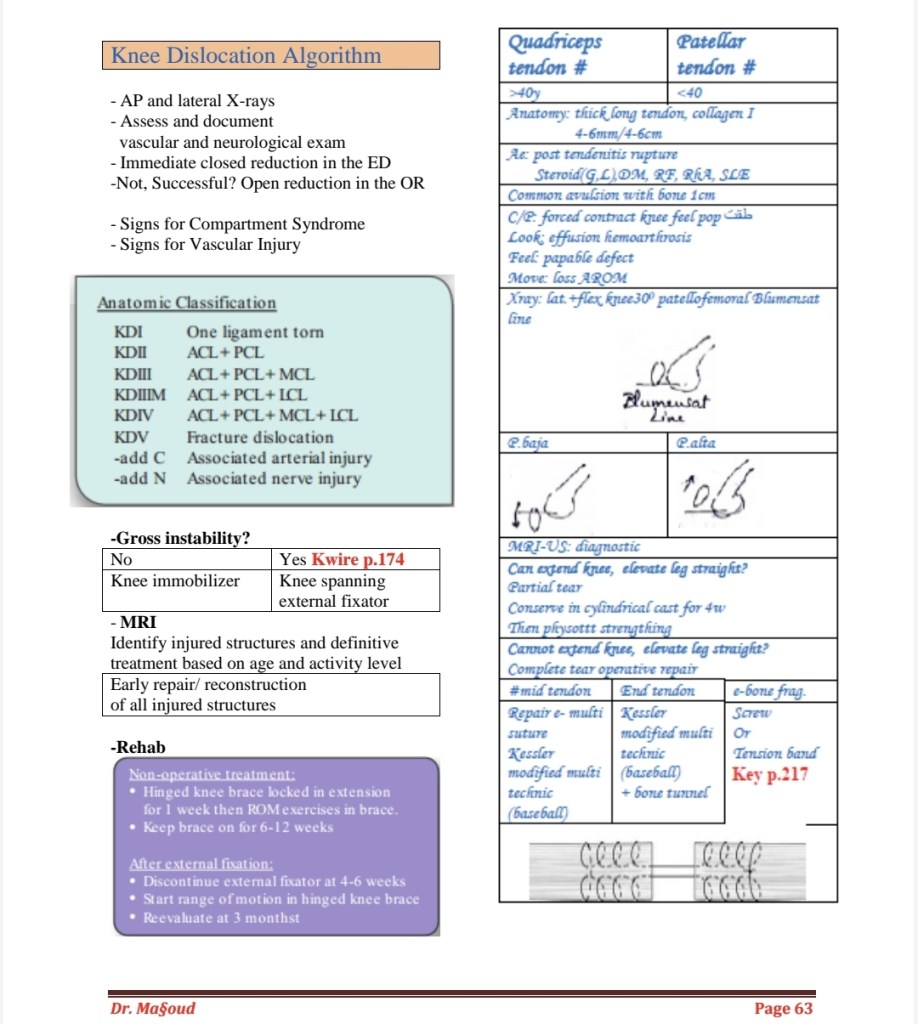

Lecture Knee dislocation & tendon injuries

Lecture Knee dislocation & tendon injuries